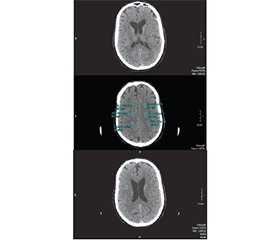

Актуальність. Акубаротравма (контузія) — ураження організму внаслідок різкого механічного впливу, що не обов’язково супроводжується механічними ушкодженнями органів і тканин. Симптоми контузії включають: дезорієнтованість, втрату свідомості (тривалість від пари хвилин до кількох годин); погіршення пам’яті або амнезію; сильний головний біль; нудоту і блювання; зміну психоемоційного стану; проблеми зі слухом і зором. Найтяжче перебігає контузія головного мозку, для якої характерний розвиток як загальних порушень (непритомність, порушення дихання, кровообігу тощо), так і пов’язаних з локалізацією вогнища ураження мозкової тканини. Черепно-мозкова травма, спричинена вибухами чи іншими подіями високої інтенсивності, потребує невідкладної допомоги. Метою дослідження є виявлення симптомів ураження зорового аналізатора у військових з акубаротравмою, щоб розробити кращі стратегії раннього виявлення, ефективного лікування і профілактики наслідків травм, що зрештою зменшить їхній вплив і поліпшить зорові функції в постраждалих під час війни. Матеріали та методи. Під наглядом перебували 5 хворих (10 очей) віком 30,0 ± 8,2 року, чоловічої статі. Застосовувались як стандартні офтальмологічні методи (візометрія, периметрія, тонометрія, біомікроофтальмоскопія, кераторефрактометрія, проба Ширмера), так і сучасні спеціальні додаткові методи обстеження — оптична когерентна томографія макули і дисків зорових нервів, комп’ютерна томографія головного мозку. Результати. За результатами обстеження майже в усіх пацієнтів спостерігалося стійке зниження зорових функцій зі змінами периферичного зору при нормальних показниках тонометрії на обох очах.

Background. Concussion is a damage to the body due to a sudden mechanical impact. Organs and tissues may remain undamaged. Concussion symptoms include disorientation, loss of consciousness (duration from a few minutes to several hours); memory impairment or amnesia; severe headache; nausea and vomiting; change in psycho-emotional state; hearing and vision problems. Brain concussion is the most severe, it is characterized by the development of both general disorders (fainting, impaired breathing, blood circulation, etc.) and those related to the localization of brain tissue damage. Traumatic brain injury caused by explosions or other high-intensity events requires immediate care. The purpose of the study is to identify symptoms of a damage to the visual analyzer in military personnel with concussion in order to develop better strategies for early detection, effective treatment and prevention of the consequences of injuries, which will ultimately reduce their impact and improve visual function in war victims. Materials and methods. Five male patients (10 eyes) aged 30.0 ± 8.2 years were under supervision. Both standard ophthalmic methods (visometry, perimetry, tonometry, biomicroophthalmoscopy, keratorefractometry, Schirmer’s test) and modern special additional examinations such as optical coherence tomography of the macula and optic nerve head, computed tomography of the brain were used. Results. According to the results of the exa-mination, almost all patients had a persistent decrease in visual functions and changes in peripheral vision with normal tonometry indicators in both eyes.